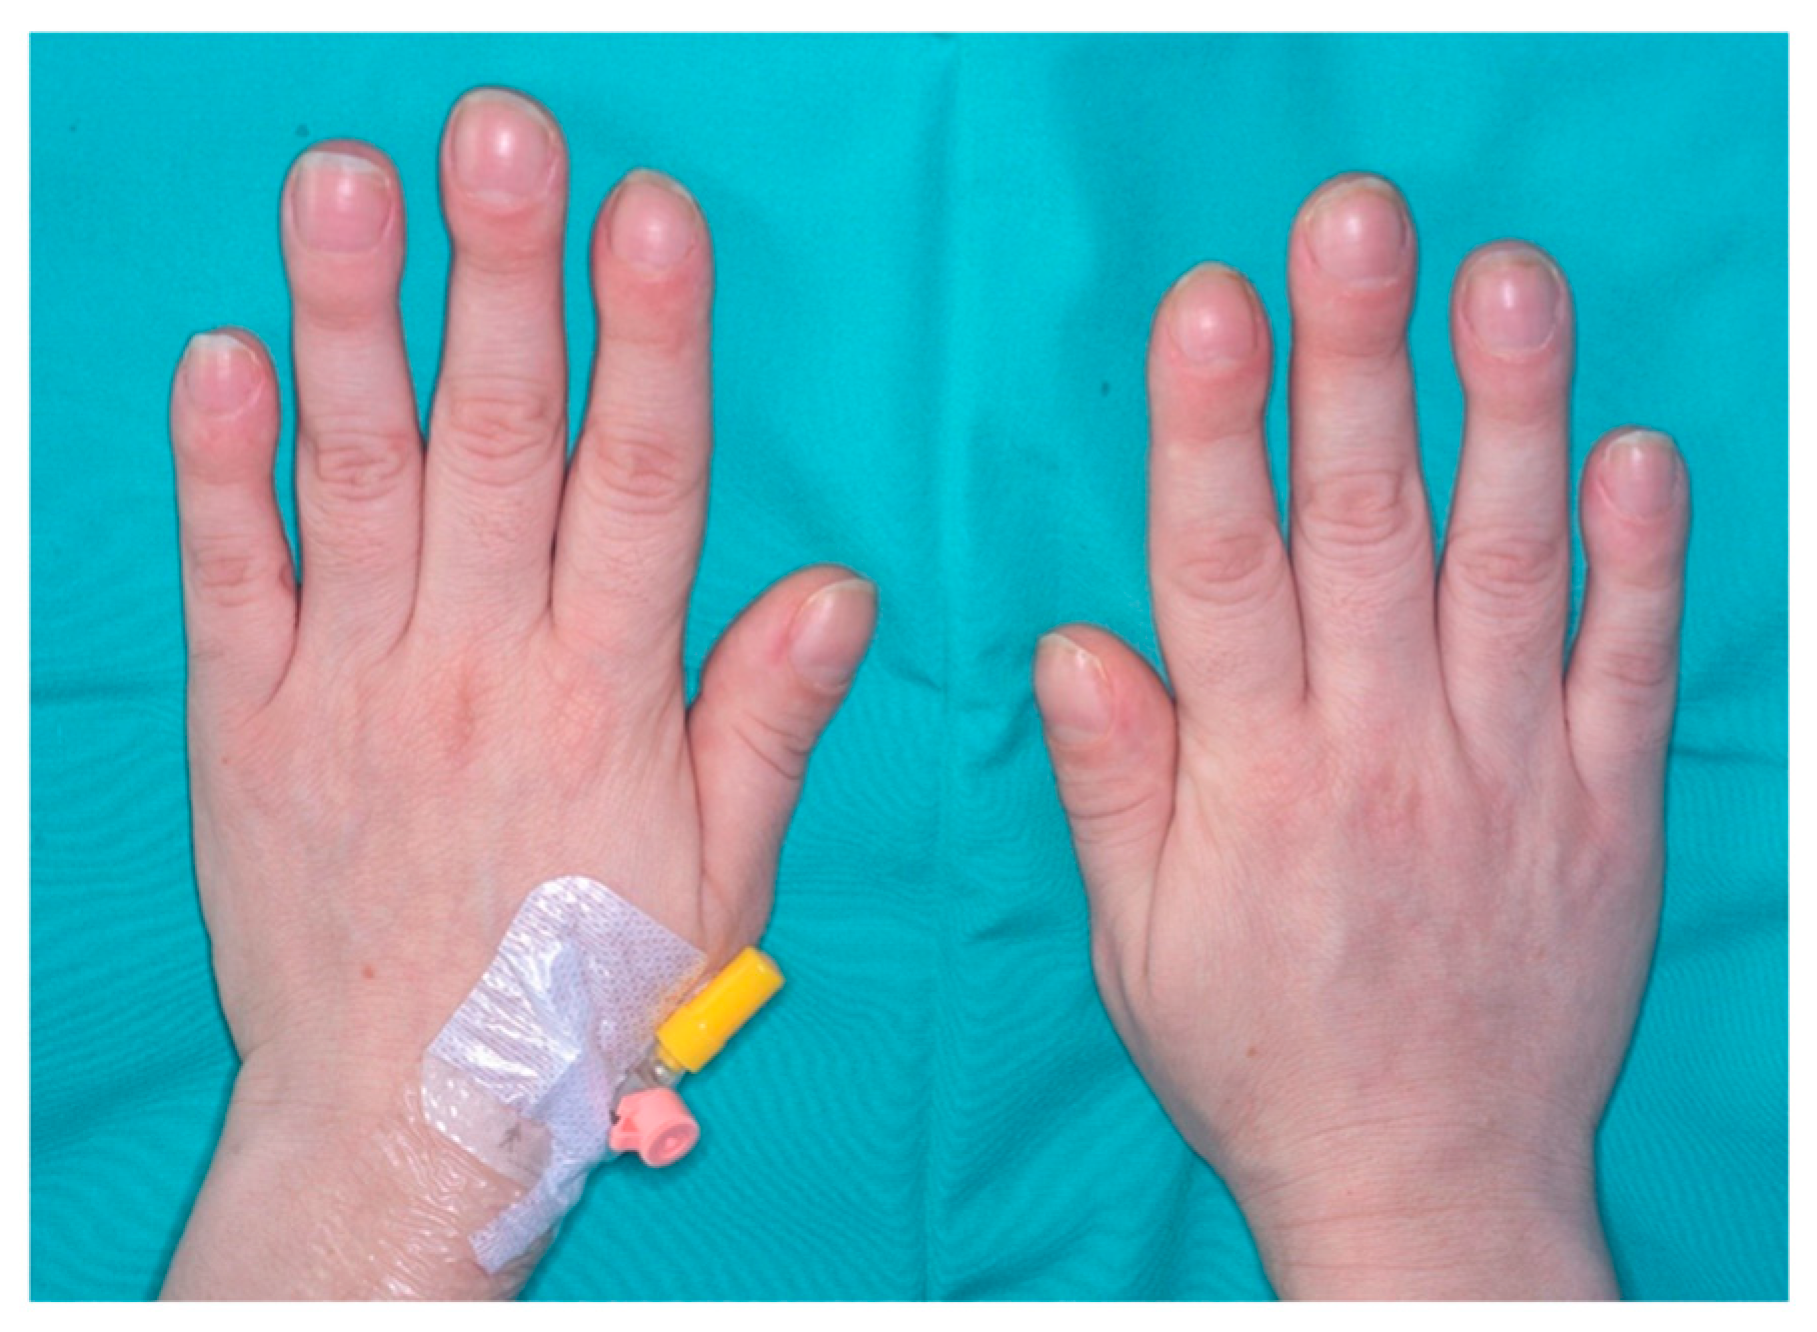

A 39-year-old woman was diagnosed with SLE and antiphospholipid antibodies 8 years ago. The chief manifestations of her disease included low-grade fever and polyarthritis. She was treated with Plaquenil and aspirin, achieving a good clinical response for the first two years. Eight months before presentation, she experienced symptoms attributed to a flare of SLE, leading to an increase in immunomodulatory treatment with no improvement. Eight months prior to her presentation, she experienced symptoms attributed to a flare of SLE, with low-grade fever, polyarthralgia with prolonged morning stiffness, worsening anemia and markedly elevated ESR and CRP, leading to an increase in immunomodulatory treatment with no improvement. She was treated with high-dose prednisone (20 mg/day) and methotrexate (15 mg/week) with no improvement; hence, Belimumab (200 mg/week) was added to her treatment regimen. She also noted painless swelling of her fingertips and toes, and pain along her shins, over the past month (

Figure 1). Two weeks prior to admission, she experienced daily fevers of 38.4 degrees, accompanied by shivers. She was referred to the emergency department due to acute-onset dyspnea to rule out pulmonary embolism (PE).

Upon admission, the patient was afebrile; her blood pressure was 97/60 mm Hg, heart rate 122 beats per minute, and oxygen saturation was 100% in room air. On physical examination, her breath sounds were normal. Since she was tachycardic, it was difficult to discern murmurs on auscultation. No splinter hemorrhages or other stigmata of endocarditis were identified. Prominent clubbing was noted in the digits of the upper and lower limbs. Initial laboratory evaluation demonstrated normochromic normocytic anemia (hemoglobin 8.2 g/dL), with normal leukocyte and platelet counts, PT 12.7 s. The blood smear showed no signs of hemolysis, and both the bilirubin and Coombs tests were normal. The blood chemistry results indicated normal electrolytes, liver, and kidney function tests, with mild hypoalbuminemia (albumin 3.4 g/dL). The C-reactive protein (CRP) level was markedly elevated 150 mg/L (normal value, <5), and the D-dimer test was mildly elevated (8 μ/mL). her electrocardiography was remarkable for sinus tachycardia, with no evidence of ischemia or right ventricular strain.

6]. While several pulmonary complications of SLE might explain the shortness of breath, progressive clubbing is not commonly observed in SLE and was a clue to the fact that something different may be developing [

The patient described here presented with digital clubbing, which preceded the onset of the other symptoms by several months. Digital clubbing, identified on physical examination by the loss of the normal angle between the nail plate and the skin, is a manifestation of hypertrophic osteoarthropathy, caused by proliferation and edema of the connective tissue. The most common form of clubbing is acquired, painless and bilateral. Clubbing was first described in association with emphysema by Hippocrates, who wrote: “The nails of the hand are bent; the fingers are hot, especially in their extremities”, and indeed, the literature review indicated that up to 80% of cases are associated with cardiovascular or chronic pulmonary disease, followed by chronic gastrointestinal or rheumatologic disease [